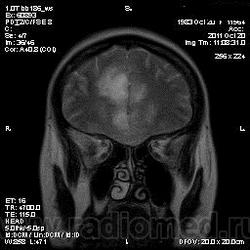

Эта же пациентка... Июль 2011 года....

В анамнезе есть зацепки на энцефалит?Мне ни разу не встречался, поэтому умничать не буду.

А здесь вариант Арнольда-Киари+ платибазия к тому же (?)

мне кажется больше похоже на диффузную глиальную опухоль. Для герпетического нехарактерна локализация и характер контрастирования. Хотя конечно нет правил без исключений..

Евгений Второй, а медиобазальные отделы височных долей - по-моему излюбленная локализация герпетических энцефалитов... Да мне кажется, что серое и белое вещество в равной степени вовлечено в процесс...

Арнольда-Киари можно указать, но вы же понимаете, что он меркнет на фоне основной патологии....

а медиобазальные отделы височных долей - по-моему излюбленная локализация герпетических энцефалитов..

Абсолютно согласен, просто у меня не все картинки раньше загрузились и показалось, что все изменения в лобных долях и базальных ядрах. Снимаю свои возражения.